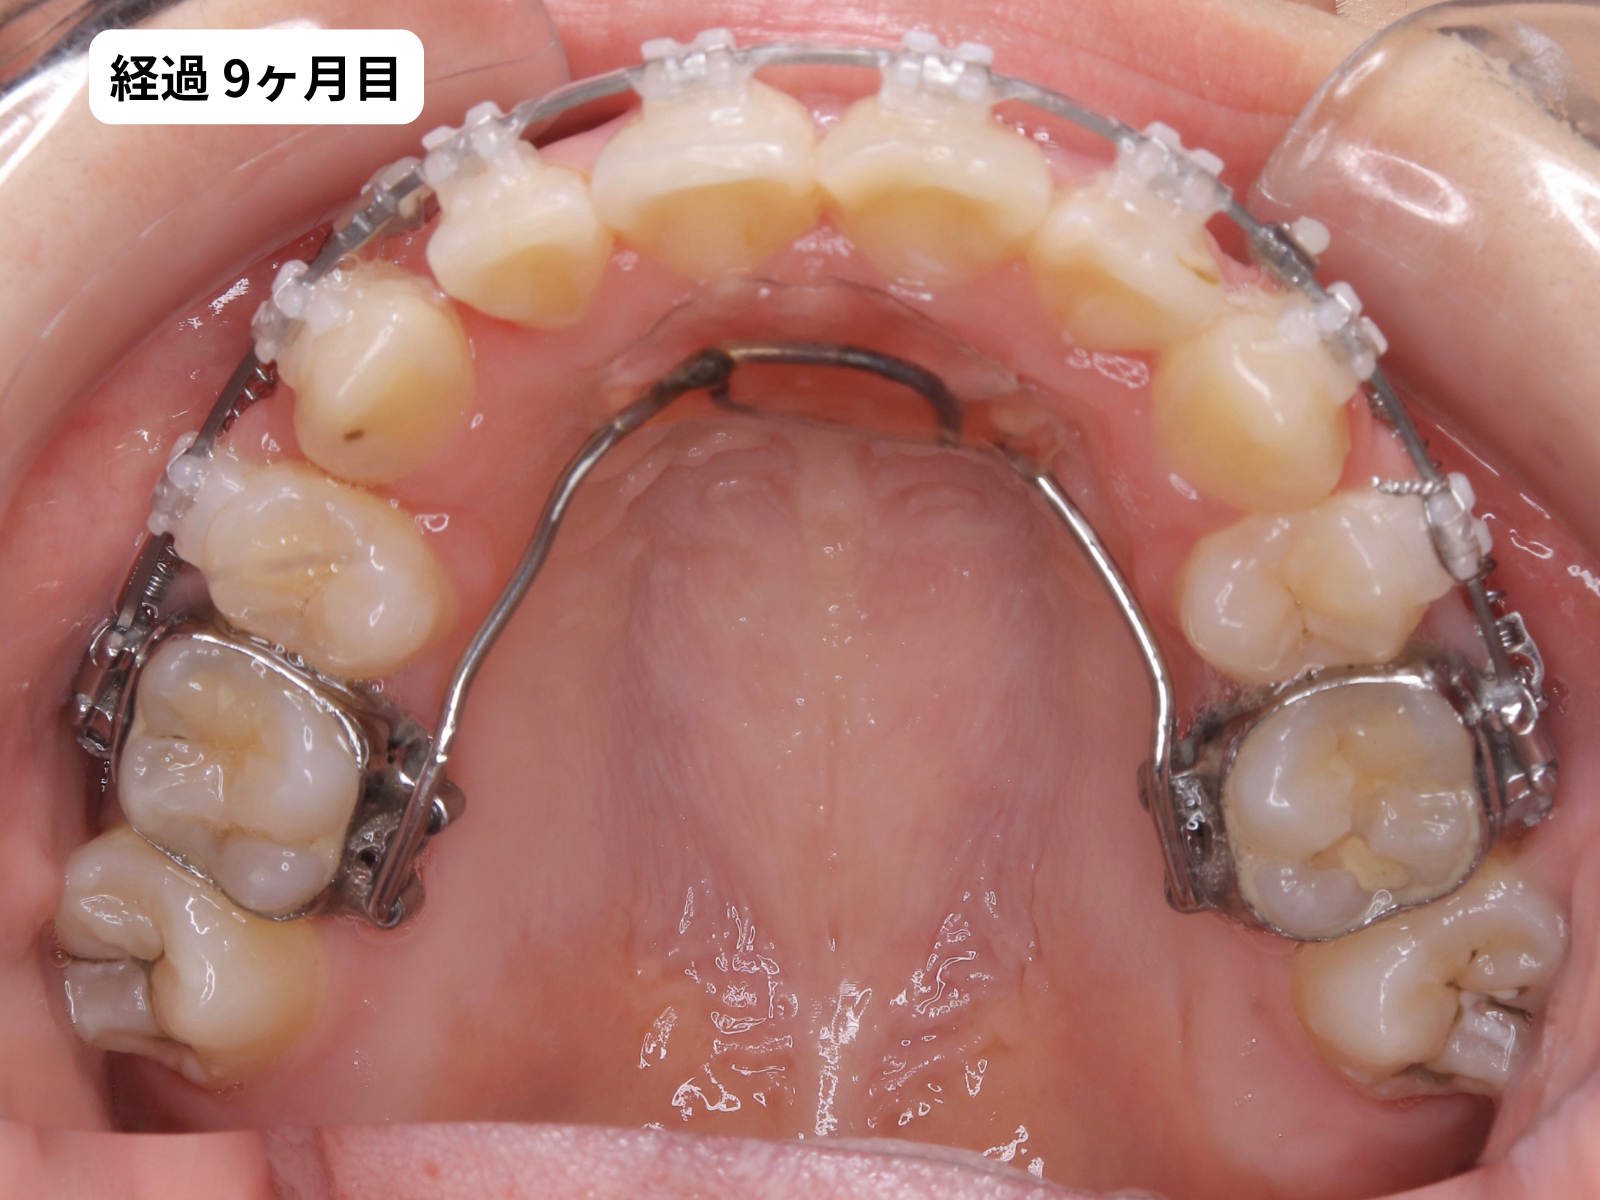

装置装着から1年2ヶ月、毎月の経過

装置をつけた後、上の歯の噛み合わせ面の写真を毎月記録しました。下のスライダーで、月ごとに歯がどう動いていったかをご覧いただけます。

毎月の写真で歯がスムーズに動いているのがわかります。これは 軽い力(約50g)でゆっくり動かす、毎回の来院で移動距離を確認する、この2つを積み重ねた結果です。